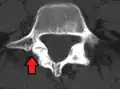

Anterolisthesis L5/S1